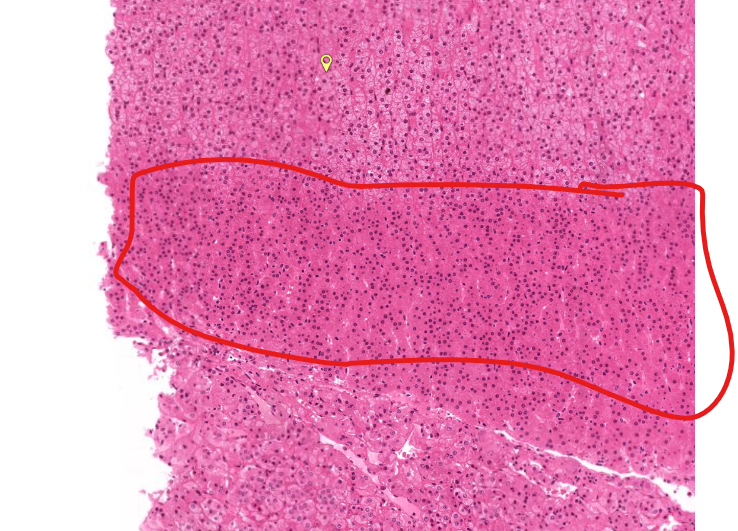

spleen

“white” pulp

made up of lymphocytes

lots of basophils

“red” pulp

filters and degrades RBCs